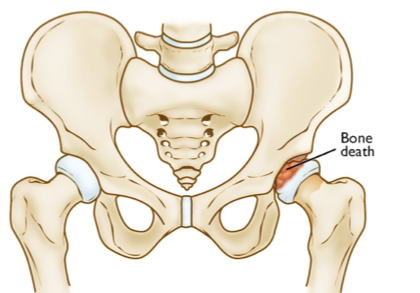

legg-calve perthes

_______________ is avascular necrosis of the hip in childhood

epiphyseal plate

legg-calve perthes is decreased blood to the ______________

3-12

5-7

legg-calve perthes occurs from ages _____-_____ but is most common from ages ______-_____

males

legg-calve perthes occurs more in (females or males)

T

T/F: maternal smoking and secondhad smoke can play a factor in a child developing legg-calve perthes

it’s the same but legg-calve perthes is non-weight bearing

what’s the difference in hip dysplasia and legg-calve perthes casting

less than 6

if the a child has legg-calve perthes and they are age ________, conservative treatment is recommended